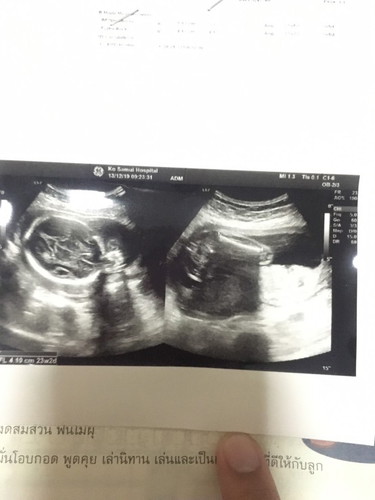

แม่ๆ ดูออกกันมั้ยค่ะ

ช่วยดูหน่อยได้มั้ยว่า ชาย หรือ หญิง

ภาพไม่ค่อยชัดนะคะ แต่ดูแล้วไม่มีจู๋ยื่นออกมา น่าจะเป็นผู้หญิงนะคะแม่ ของเราเป็นภาพตรงหว่างขาจะมียื่นๆออกมาแบบนี้ ได้ลูกชายค่ะ